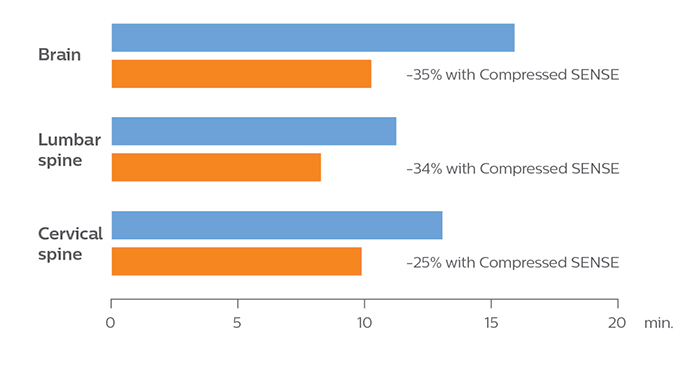

“We started scanning with a new set of ExamCards in which several sequences were replaced by sequences with Compressed SENSE,” says Dr. Koyasu. “We performed only a little further tailoring of ExamCards to meet our preferences. And as a result, we now can scan four brain exams per hour instead of only three before using Compressed SENSE.” The KNC team significantly reduced the scanning time of their most used ExamCards, see table and diagram.

Reduction of scanning time with Compressed SENSE

in ExamCards of KOYASU Neurosurgical Clinic

| KNC ExamCard | Total scan time before | Total scan time with Compressed SENSE | Change |

| Brain | 15:48 min. | 10:19 min. | -35% |

| Cervical spine | 13:11 min. | 9:52 min. | -25% |

| Lumbar spine | 11:41 min. | 8:17 min. | -34% |

With Compressed SENSE, the scan time for the routine brain examination at KNC was reduced from 15:48 to 10:19 minutes, which corresponds to 35% reduction.

With Compressed SENSE, the scan time for the routine cervical spine examination at KNC was reduced from 13:11 to 9:52 minutes, which corresponds to 25% reduction.

which corresponds to 34% reduction.

With Compressed SENSE, the scan time for the routine lumbar spine examination at KNC was reduced from 11:41 to 8:17 minutes,